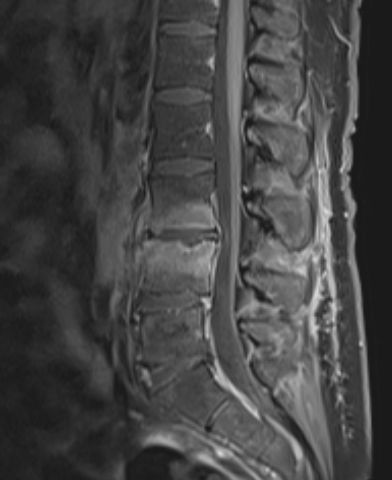

MR helrygg med kontrast, sensitivitet och specificitet ca 93-97 %, vid negativ MR men fortsatta symtom kan ny MR göras efter några dagar [3].

Spondylodiskit L3-L4, T1-viktad MR-bild med gadoliniumkontrast